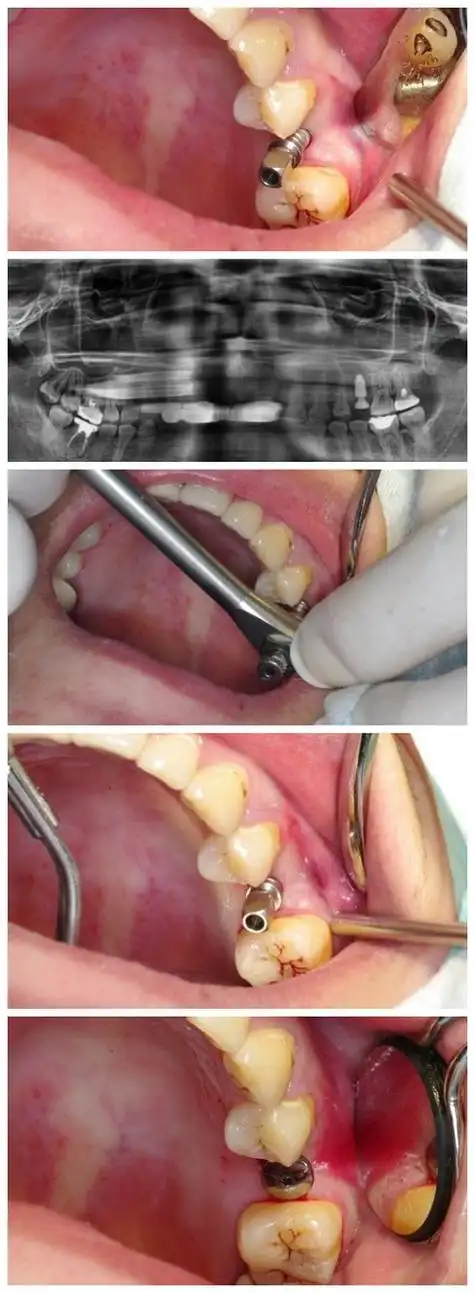

种植牙步骤种植牙步骤先介绍下本人,张永刚:口腔主治医师,同济大学